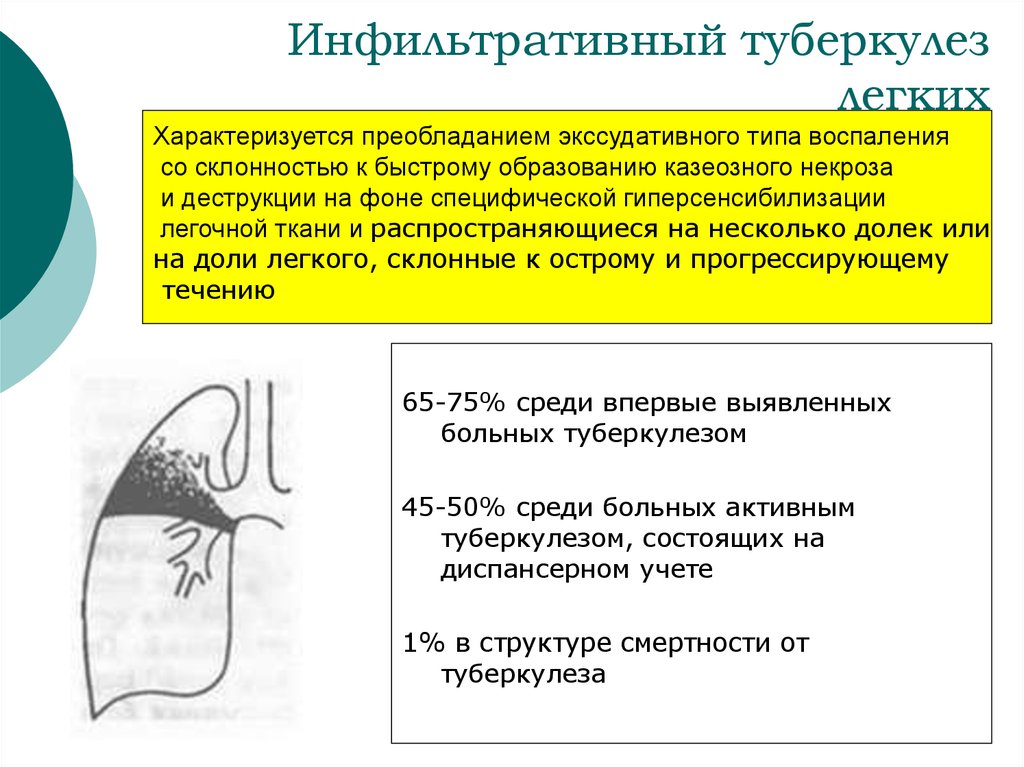

Очаговый и инфильтративный туберкулез презентация - 94 фото